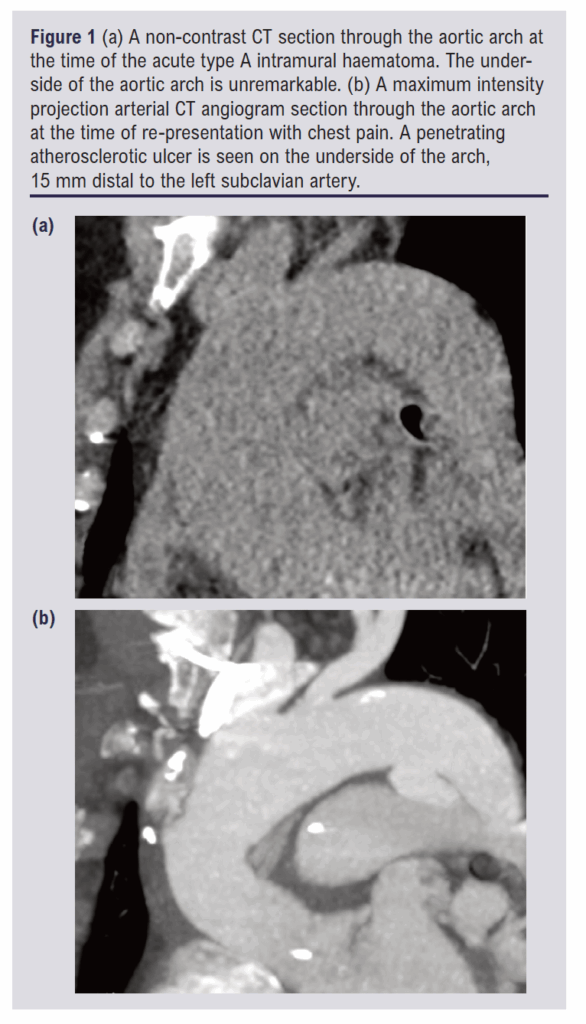

The PAU was a new finding (not present on the original CT scan 15 weeks earlier) with a depth of 10 mm and width of 21 mm. It was an isolated lesion, located 15 mm beyond the origin of the left SCA. There were no clinical or laboratory signs of infection to suggest it may be mycotic. The two CT scans are shown in Figure 1. The aorta was maximally 29 mm between the left SCA and the left common carotid artery (CCA). Beyond the left SCA there was no aortic measurement above 26 mm. There was 16 mm of length between the middle of the left SCA and the proximal left CCA. The calibre of the left SCA was 10 mm. These measurements were suitable for a 31 mm TBE device with an 8 mm portal.